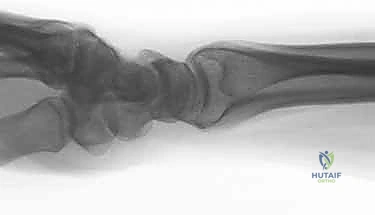

- تشوه مرئي (Deformity): في حالات الانزياح الكبير، قد يبدو الرسغ معوجاً أو منحنياً بشكل غير طبيعي. يُعرف التشوه الكلاسيكي باسم "تشوه شوكة العشاء" (Dinner Fork Deformity)، حيث ينزاح الرسغ للخلف.